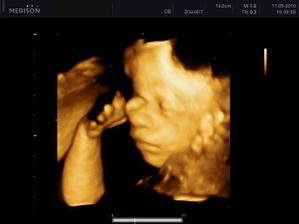

11.05. - (26+5) dnes jedeme na video

video se povedlo, máme asi 6 cca 5 - 10ti vteřinových videíí.Bylo to super. Karolínka se zase mlela jako drak. Je taková živoučká 😀

kontrola - vše v pořádku a máme + 8kg